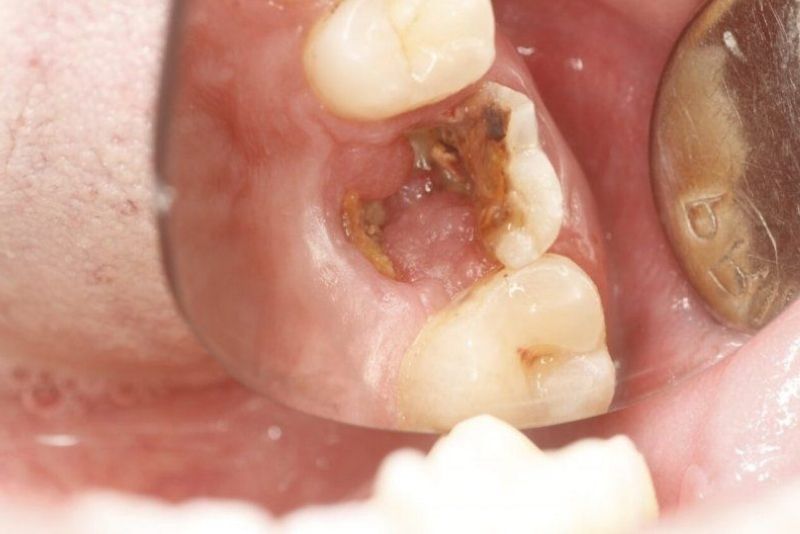

Răng bọc sứ bị viêm tủy cần thăm khám sớm

2. Dấu hiệu răng bọc sứ bị viêm tủy

Dưới đây là các dấu hiệu thường gặp khi răng bọc sứ bị viêm tủy. Tình trạng này thường xuất hiện sau vài tuần đến vài tháng nếu răng có bệnh lý tiềm ẩn hoặc mão sứ không khít.

- Đau âm ỉ hoặc đau nhói bất chợt, không theo chu kỳ. Cơn đau có thể lan lên thái dương hoặc vùng hàm

- Ê buốt khi uống nước lạnh hoặc ăn nóng nhẹ

- Răng đau rõ rệt mỗi khi hai hàm chạm nhau

- Viêm nướu vùng rìa mão khiến vi khuẩn dễ tấn công vào chân răng và tủy

- Mùi hôi xuất hiện dai dẳng do mô tủy viêm hoặc mão sứ hở viền tích tụ vi khuẩn

- Răng bị viêm tủy lâu ngày có thể chuyển màu xám hoặc tối hơn so với các răng bên cạnh